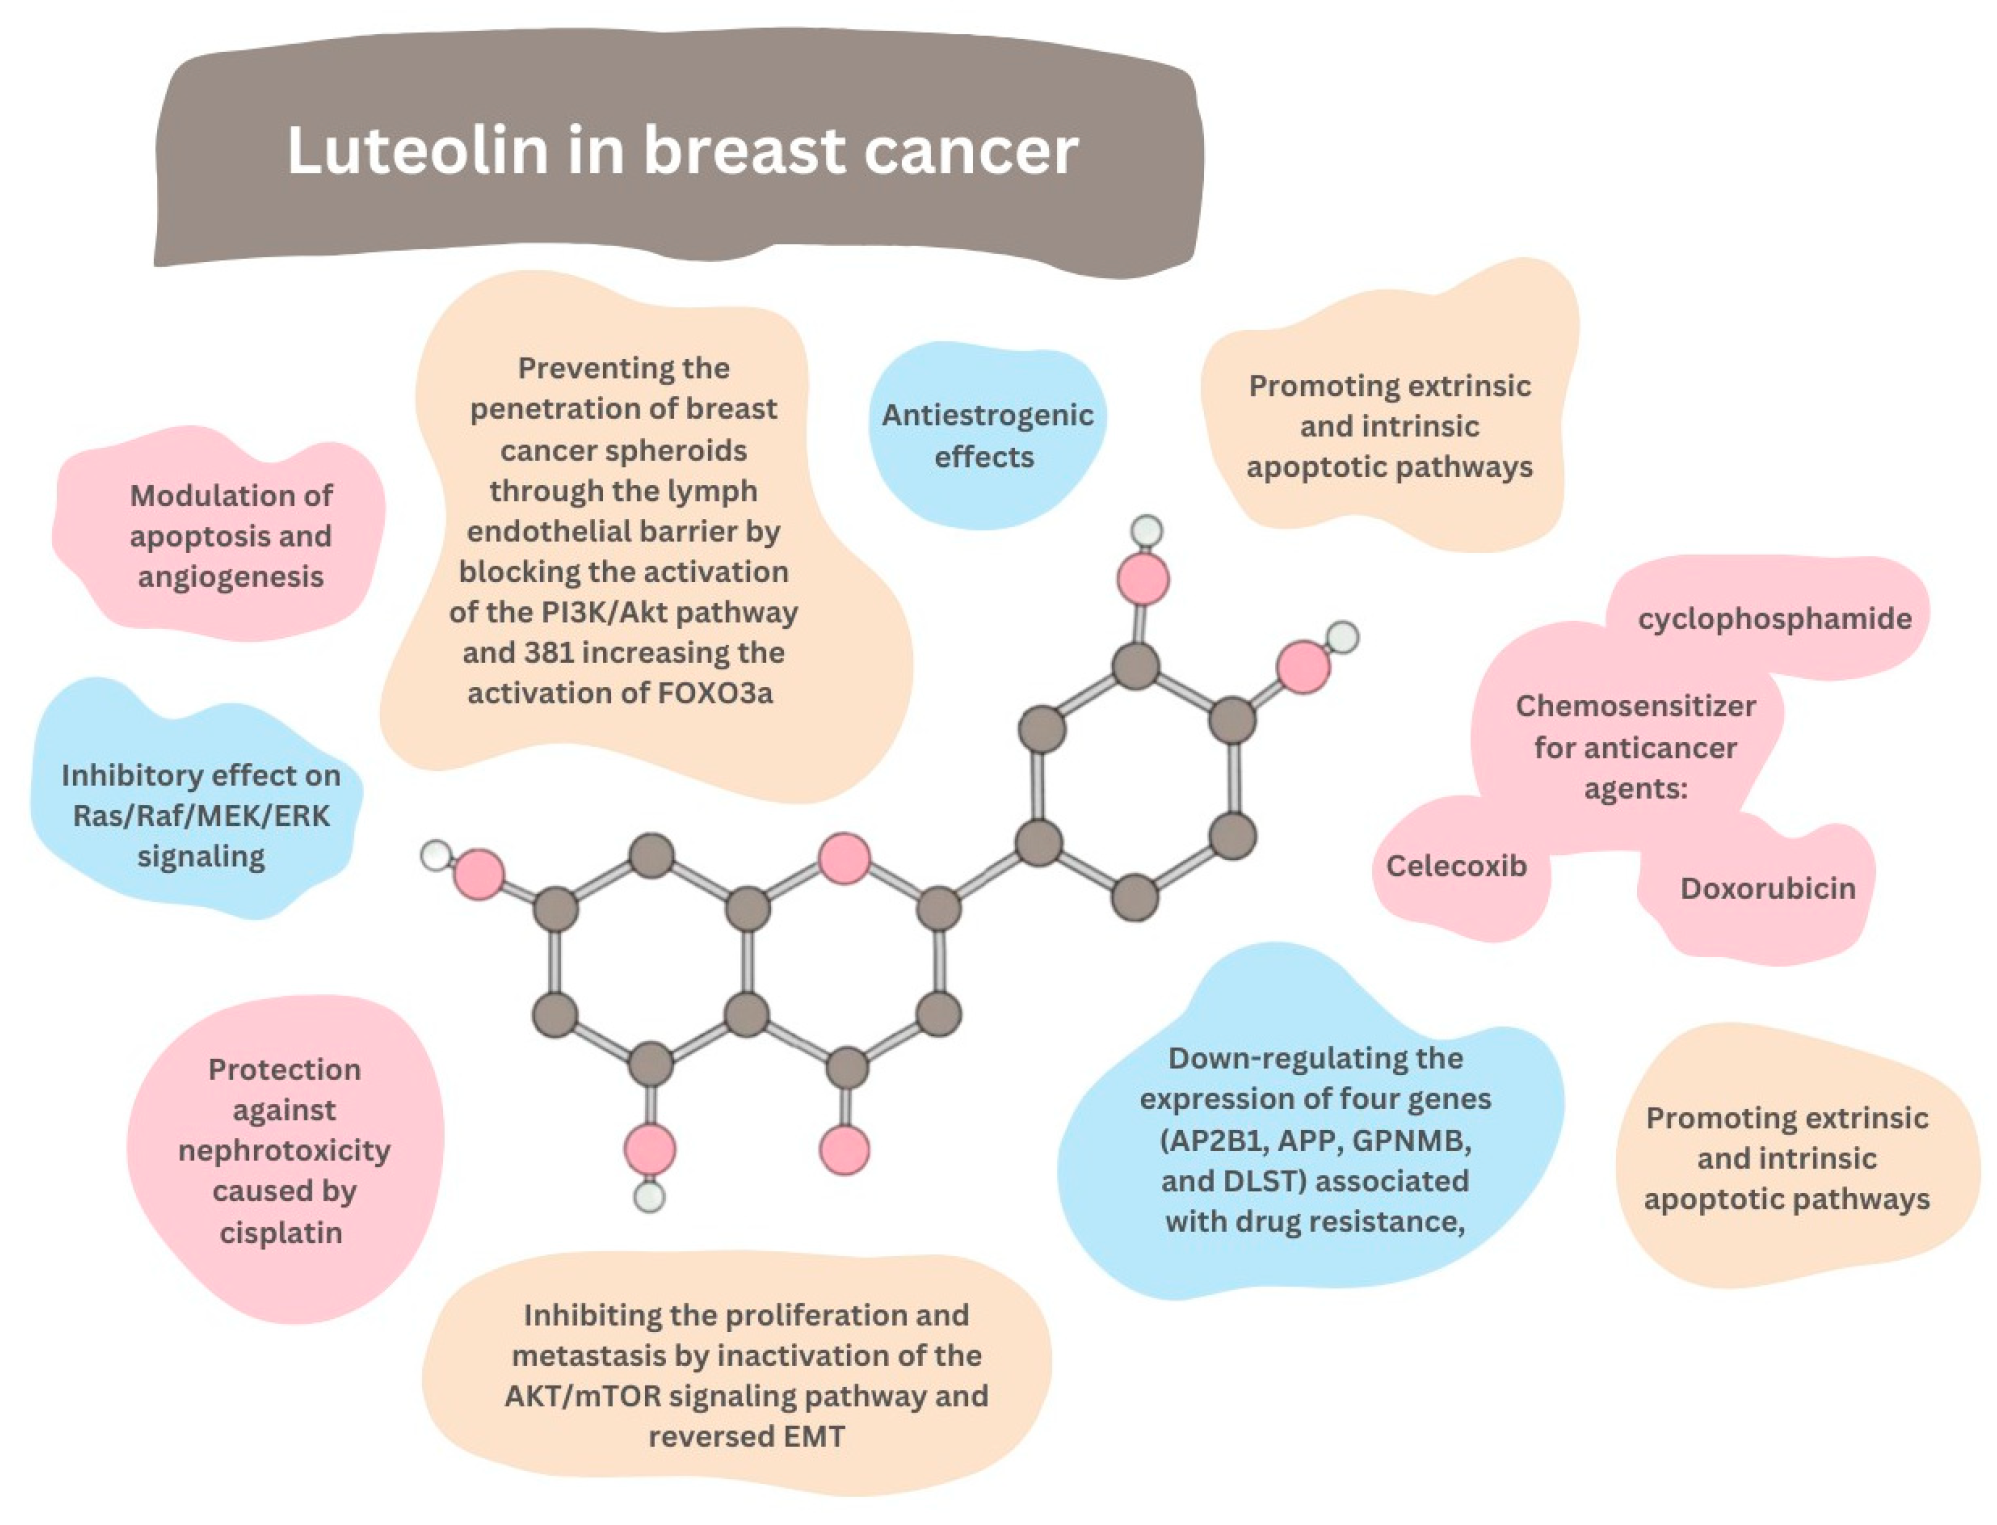

8. Breast Cancer

- Block the proliferation of IGF-1-stimulated luminal A subtype ERα-positive MCF-7 cells;

- Suppress the growth of triple-negative/basal-like ERα-negative MDA-MB-231 cells;

- Decrease the viability of breast cancer cells MCF7/6 and MDA-MB231-1833;

- Reduce the tumor burden in nude mice inoculated with MDA-MB-231 cells;

- Inhibit the migration and invasion of highly metastatic triple-negative breast cancer (TNBC) cell lines MDA-MB-231 and BT-549;

- Suppress the formation of lung metastases in breast cancer xenograft tumors originating from MDA-MD-231 cells;

- Inhibit the migration of ERα-positive MCF-7 cells;

- Inhibit the migration and viability of human MDA-MB-435 and MDA-MB-231 cells;

- Reverse the epithelial–mesenchymal transition (EMT) of MDA-MB-231 and BT5-49;

8.1. MicroRNAs

8.2. IGF-1 Pathways

8.3. Kinases

9. Chemosensitization

9.1. Doxorubicin

9.2. Celecoxib

9.3. Cyclophosphamide